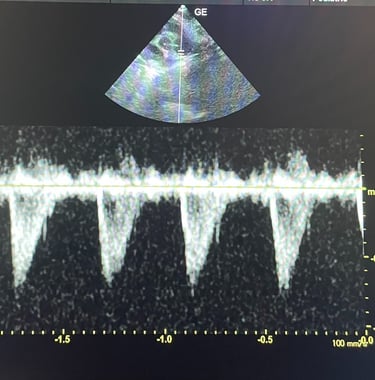

BADANIE ECHOKARDIOGRAFICZNE: badanie serca przy użyciu wysokiej klasy sprzętu ultrasonograficznego, który umożliwia wykrycie wad wrodzonych, chorób zwyrodnieniowych zastawek, powiększenia serca.